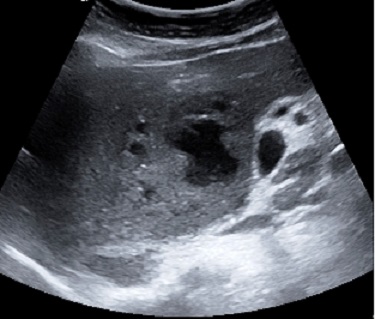

Image echographique

d'une abces du foie lobe droit : Aspect

multilobulaire a hypoechogene avec paroi tres

epaisse |